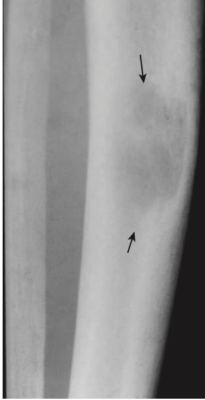

- Các tổn thương huỷ xương có biên rõ trong các xương dài, được gọi là các khối u Brown và hình ảnh dạng muối tiêu (salt-and-pepper) của xương sọ (Hình -4).

- (Các khối u Brown là những tổn thương lành tính biểu hiện sự tái hấp thu xương của một vùng khu trú của vỏ xương và thay thế bằng mô sợi và máu. Hàm lượng hemosiderin cao của chúng tạo một màu nâu đặc trưng vì thế có tên gọi là u Brown là màu nâu)